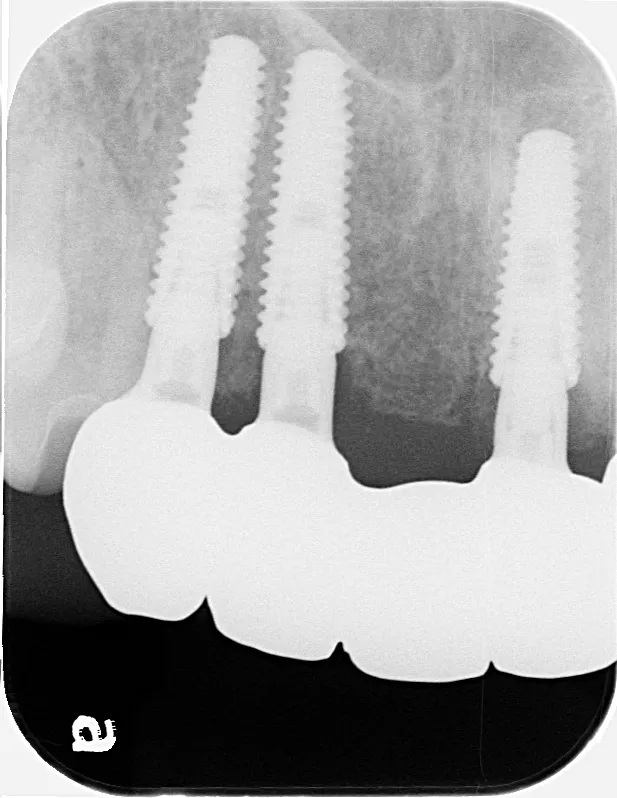

左下67 欠損に対してインプラント治療を行った症例

部分床義歯を使用していたが、どうしても慣れない上にしっかり噛むことができないためインプラント治療を希望